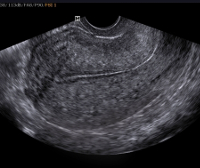

В послеродовом периоде активное наблюдение — измерение пульса, АД, контроля выделений из половых путей, УЗИ матки.

Инструментальные исследования: ЭКГ, мониторинг родов, кардиотокография, УЗИ матки. Допплерометрическое исследование — по показаниям.

• Гинекологическое УЗИ. Соединительнотканный рубец отличается неровным или прерывистым контуром, миометрий обычно истончен. В маточной стенке определяется много гиперэхогенных включений.

Полученные в ходе исследований данные учитывают при планировании следующей беременности и разработке плана ее ведения. С конца 2-го триместра таким беременным раз в 7-10 дней выполняют УЗИ рубца на матке. Рекомендованы УЗИ плода, допплерография плацентарного кровотока. При подозрении на угрожающий разрыв по рубцу в родах с помощью наружного акушерского исследования оценивают форму матки и ее сократительную активность. В ходе УЗИ определяют состояние рубцовой ткани, выявляют участки истончения миометрия или его дефекты. Для наблюдения за плодом применяют ультразвуковое исследование с допплерометрией и кардиотокографию.